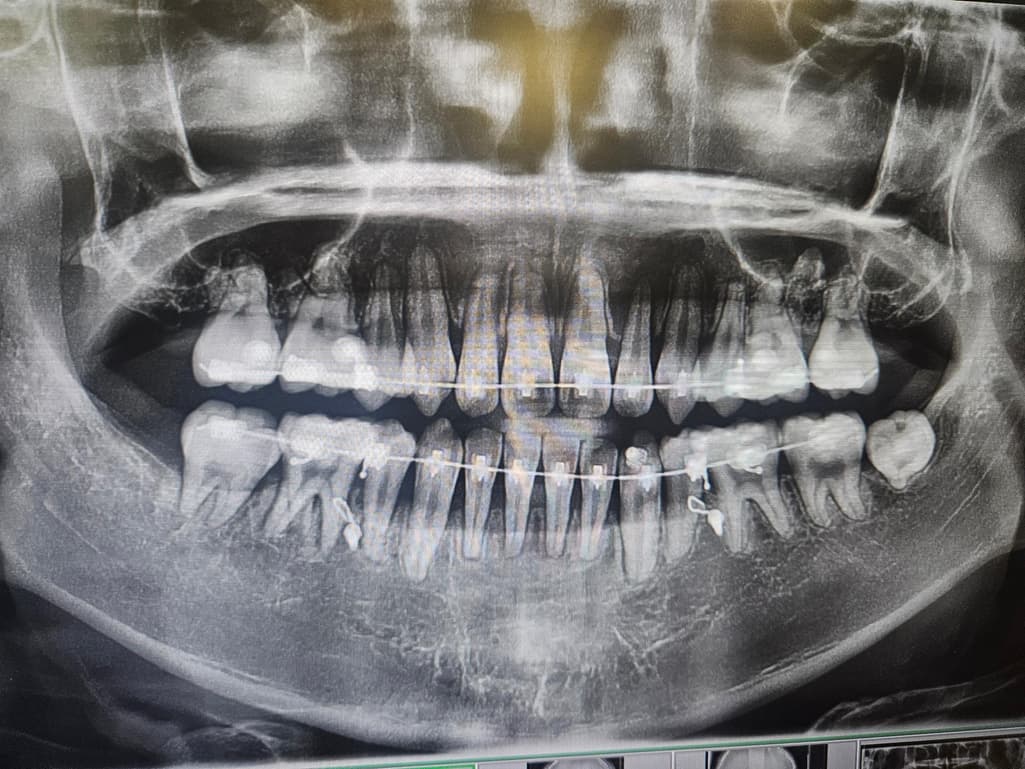

첫번째가 교정 시작할 때, 두번째가 현재입니다.

약 2년정도 되었고 육안으로 보기에도 잇몸이 많이 내려간 것 같은데 의견이 궁금합니다.

잇몸뼈가 꽤 내려간 것으로 보입니다. 교정 후에도 잇몸관리를 잘해주셔야 할 것 같습니다.

사진으로 갔을 경우에는 치조골의 양이 어느 정도 내려간 것으로 보입니다. 치즈볼의 양이 내려갔을 경우 치아를 잡고 있는 치조골의 양이 줄어들었기 때문에 잇몸에 염증이 생기지 않도록 주의해서 관리를 하는 것이 좋습니다.

엑스레이 사진으로는 잇몸이 아니고 잇몸뼈 상태를 관찰합니다. 교정 후로 잇몸뼈가 다소 낮아지고, 치아 뿌리도 짧아진 것이 관찰은 되지만 엄청 심각한 편은 아닙니다. 앞으로 관리 잘해주시면 됩니다. 교정 후 잇몸, 잇몸뼈 수축 그리고 치근 흡수 부작용은 얼마든지 있을 수 있습니다.